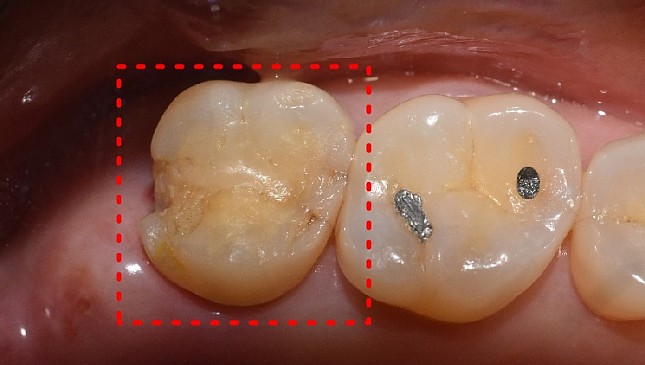

치아살리기 치료 전후 사진

잇몸재생교정 치료 전후사진

잇몸 전체가 무너져 동시다발적으로 죽어가던 치아들을 한꺼번에 살려 냅니다.